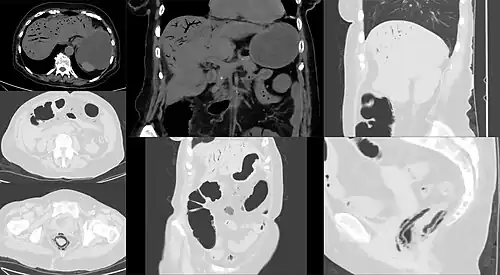

| Computed tomography (CT) showing dilated loops of small bowel with thickened walls (black arrow), findings characteristic of ischemic bowel due to thrombosis of the superior mesenteric vein. | |